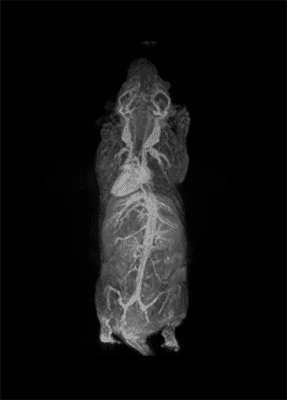

MRI is based on NMR Spectroscopy, which is the best language to talk to nature. We know how it is important to exploit different field strengths in order to extract maximum information from the system that we are investigating.

I think that also the low-field, let’s say the low/intermediate field to work at the 1 Tesla for instance as in the case of this beautiful Icon system, this gave us unique possibilities. Anytime we use a gadolinium-based agent or more in general a paramagnetic basic agent the best field is the 1 Tesla.

So, we can show that there is a real advantage of working at 1 Tesla in comparison to for instance 7 or 9 Tesla when one is using a relaxation enhancer to target a specific epitope in the region of interest.